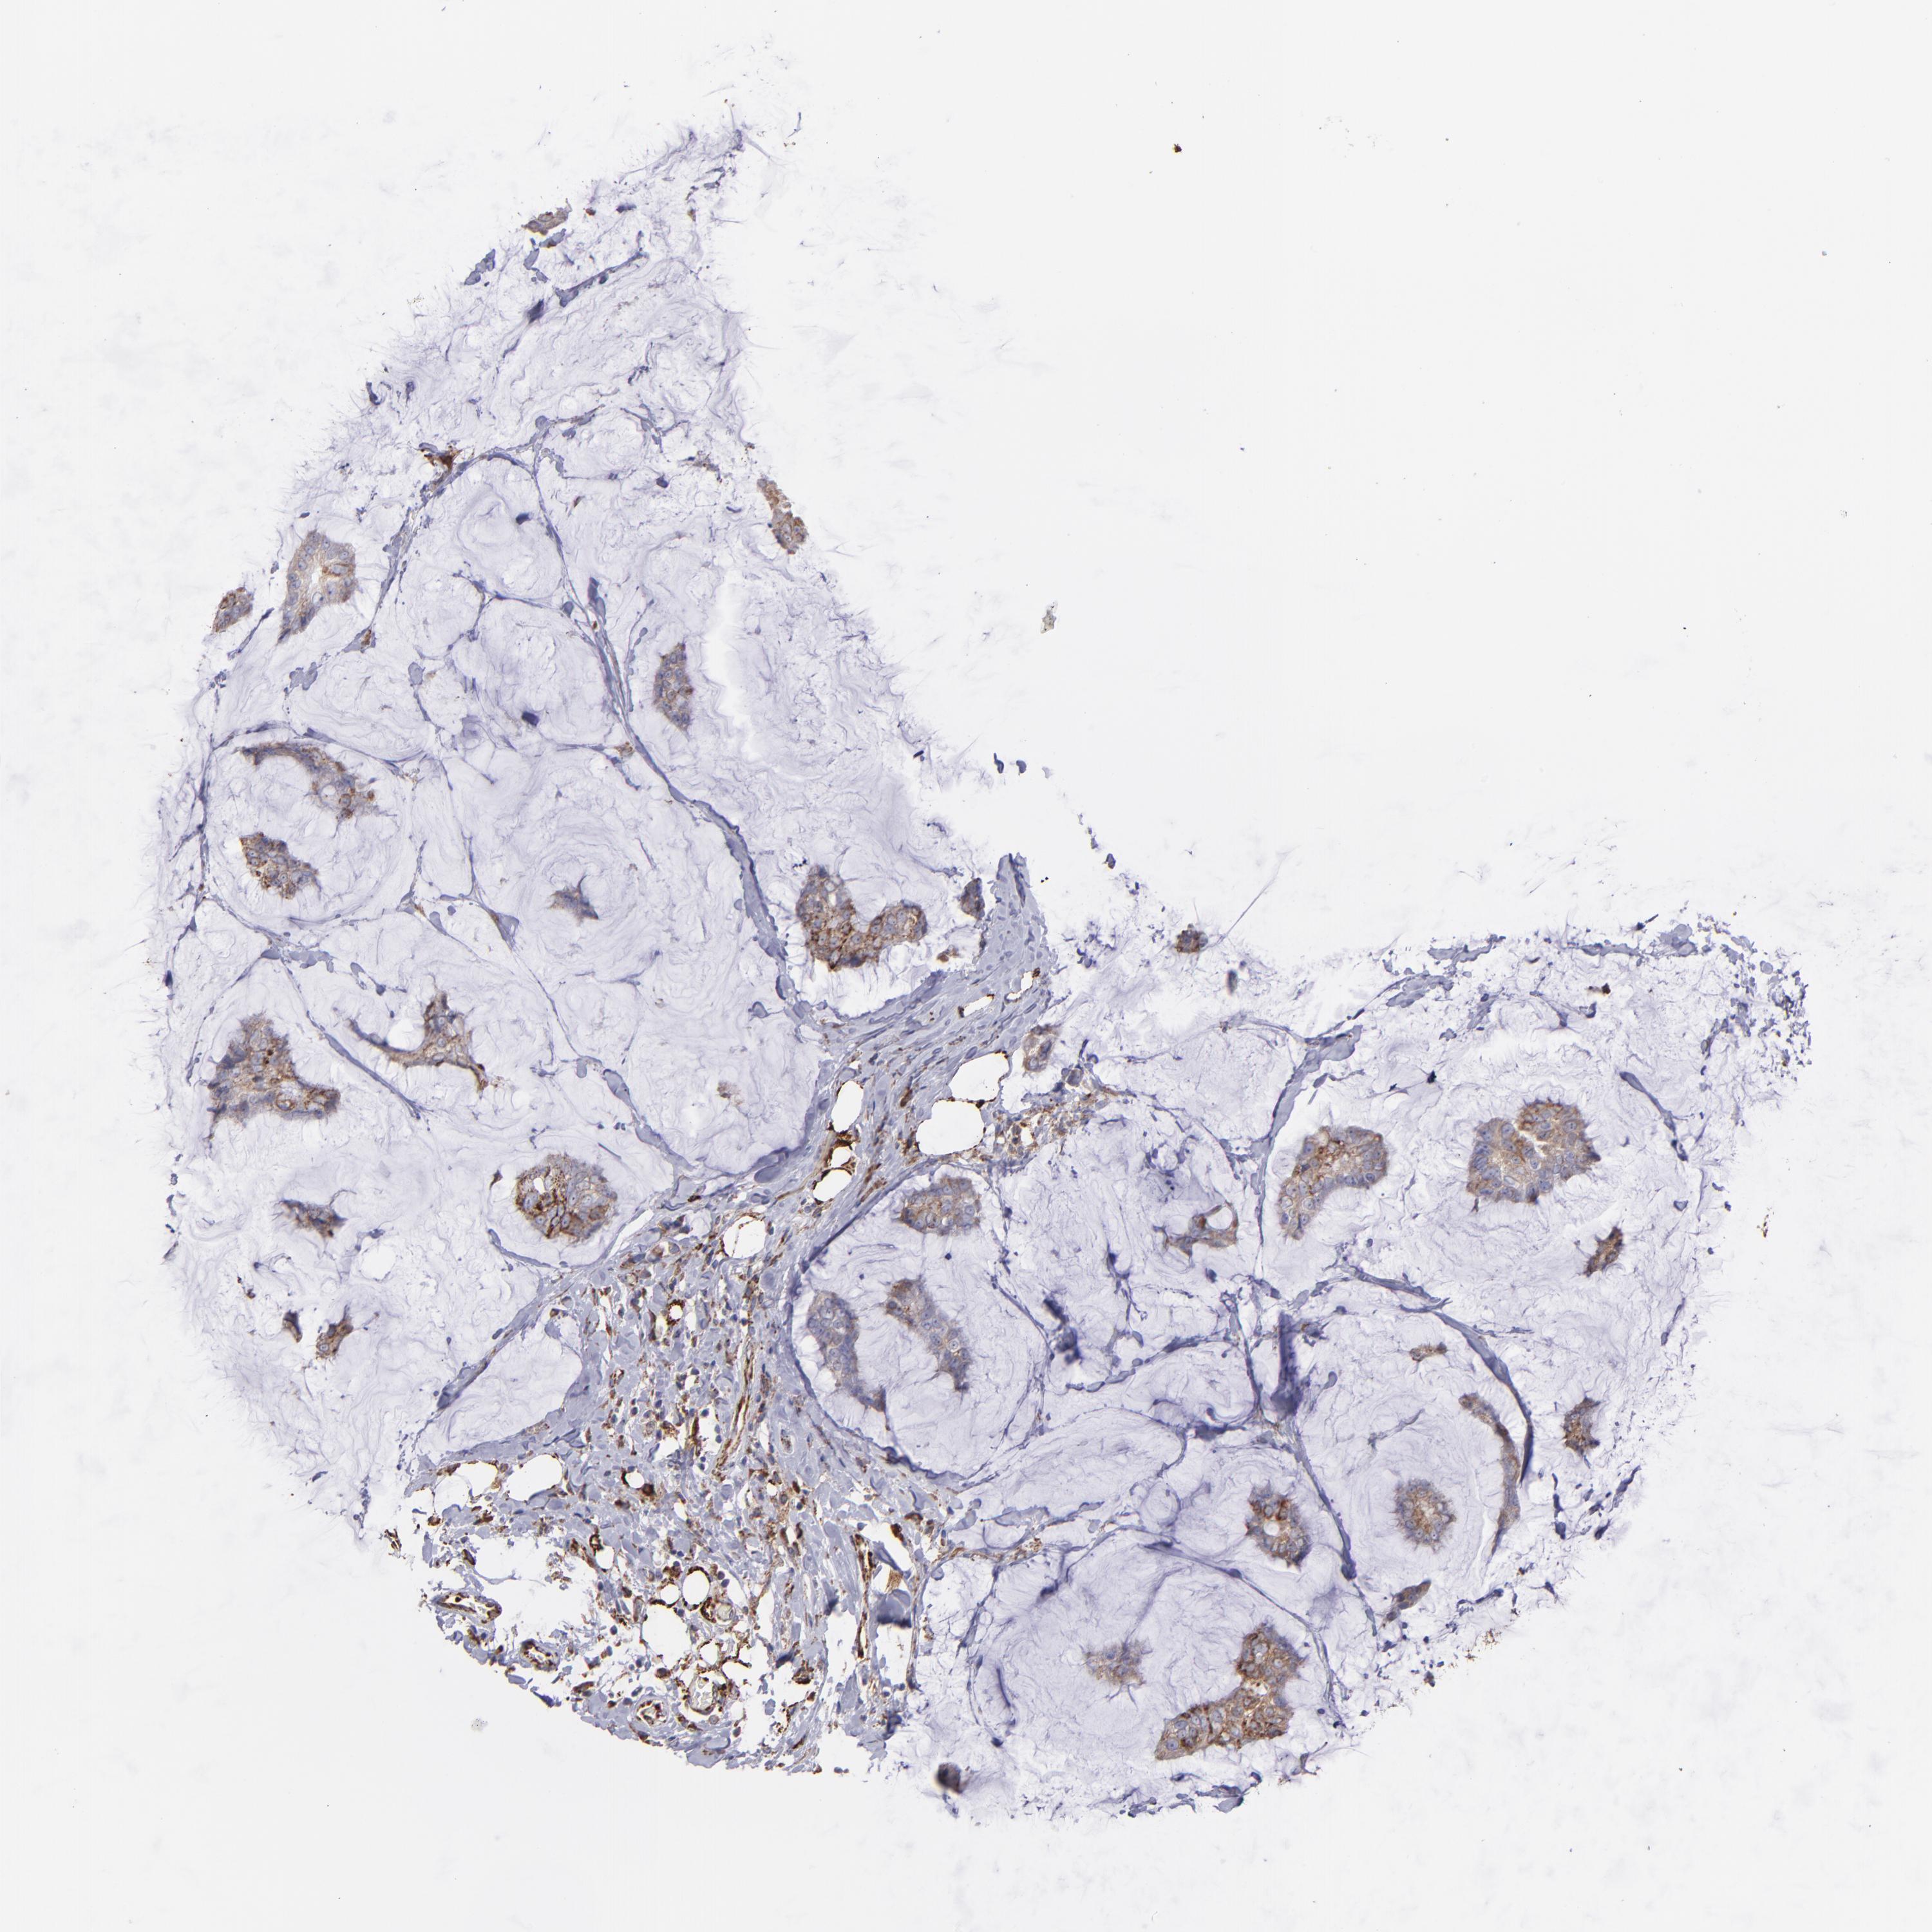

CANCER BREAST CANCER Show tissue menu

BRCA TCGA BRCA VALIDATION PROTEIN EXPRESSION